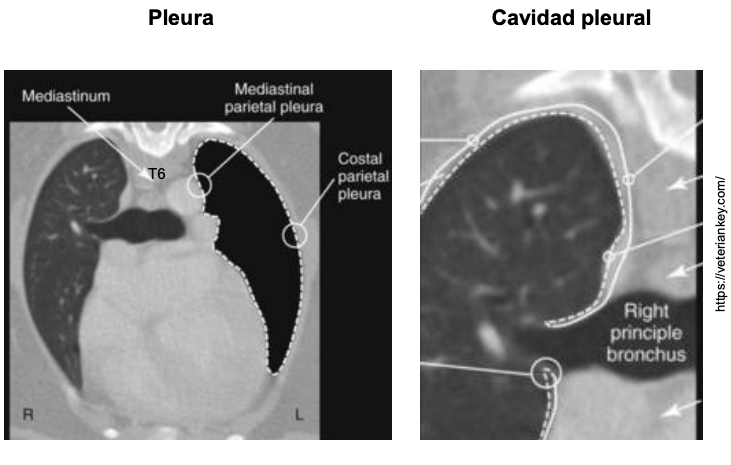

- Pulmones + Pleura

- Cavidad pleural

- Mediastino